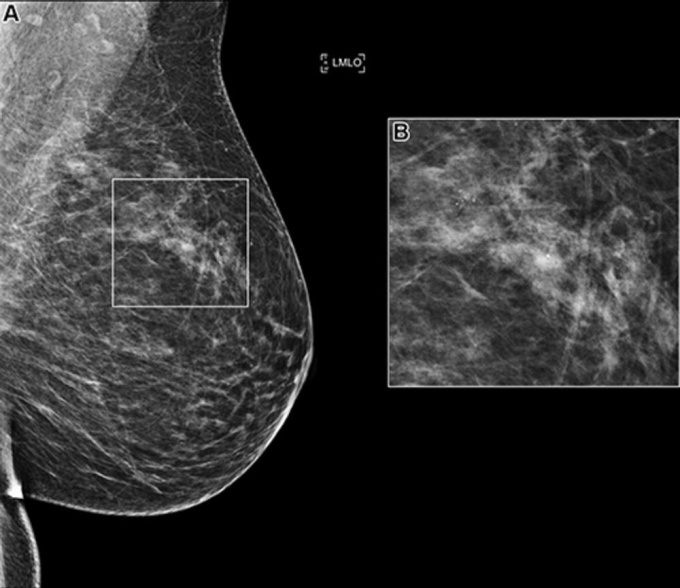

The RSNA Screening Mammography Breast Cancer Detection AI Challenge, held in 2023, drew more than 1,500 teams worldwide. Participants were tasked with developing artificial intelligence models capable of detecting breast cancer in screening mammograms.

Chen’s team evaluated 1,537 algorithms using a test set of 10,830 single-breast exams that were confirmed by pathology as positive or negative for cancer. The training dataset included approximately 11,000 breast screening images provided by Emory University in Atlanta, Georgia, and BreastScreen Victoria in Australia. Participants could also use publicly available data.